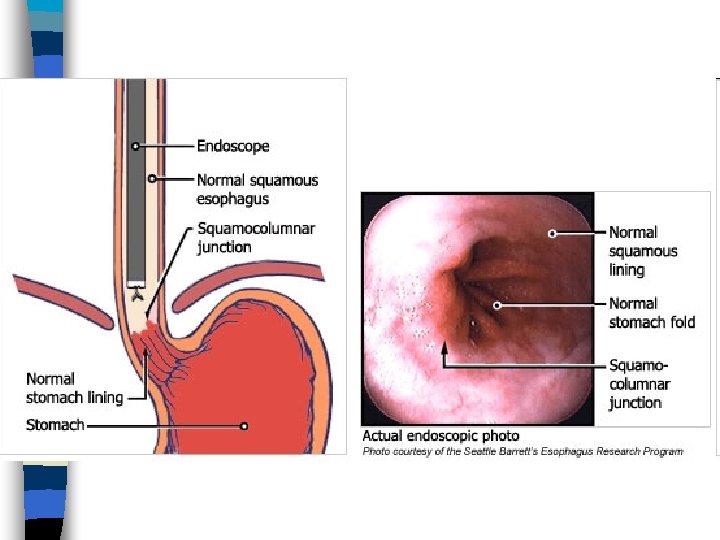

Barrett’s Esophagitis n Normal stratified squamous epithelium of distal esophagus replaced by: – Metaplastic, columnar, glandular intestinelike mucosa n Can give rise to adenocarcinoma n Warrants frequent surveillance by endoscopy